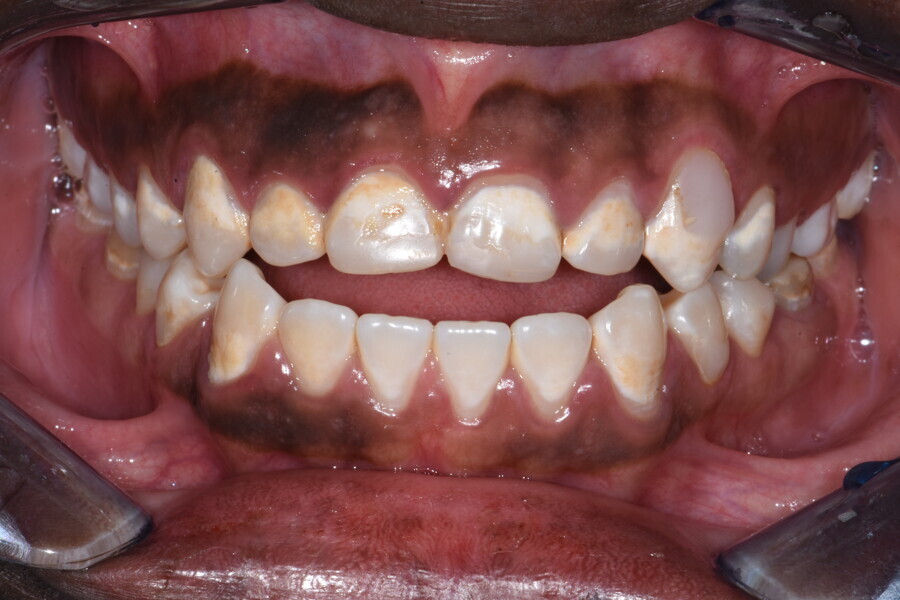

The 58-year-old patient wished to improve his oral aesthetics and function, complaining of mobility of the posterior teeth and wear of the anterior teeth. After data collection, a very complex situation was identified (Figs. 11–13):

1. severe periodontitis with poor prognosis of some teeth;

2. anterior crossbite;

3. severe wear mainly of the anterior teeth and compensatory eruption;38

4. atypical swallowing and lower posture of the tongue at rest;

5. masticatory dysfunction during the mastication test; and

6. no significant signs of temporomandibular disorder.

This patient, like all patients requiring interdisciplinary rehabilitation, had to first undergo periodontal treatment and caries restoration (Fig. 17). At the same time, it was important to rehabilitate swallowing with Froggymouth and relax the masticatory muscles and relieve the TMJs with an occlusal device. We could then study the orthodontic treatment plan using Invisalign ClinCheck (Align Technology) and showed the treatment plan to the interdisciplinary team and to the patient (Fig. 18). We were then able to create the correct sequence of orthodontic treatment, bone augmentation and implant surgery needed for the posterior edentulous spaces.